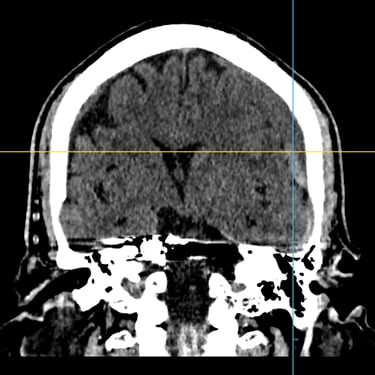

Hematoma subdural subagudo: evacuación mediante burr hole ampliado

El hematoma subdural subagudo se caracteriza por la acumulación progresiva de sangre entre la duramadre y la superficie cerebral, generalmente posterior a un traumatismo craneal. Esta condición puede generar síntomas como dolor de cabeza persistente, confusión, debilidad en extremidades o alteración del estado de conciencia. El tratamiento quirúrgico consiste en la evacuación del hematoma mediante burr hole ampliado, técnica que permite realizar un orificio en el cráneo para drenar el contenido hemático y descomprimir el cerebro. Este procedimiento ayuda a disminuir la presión intracraneal, mejorar los síntomas neurológicos y prevenir complicaciones asociadas a la compresión cerebral.